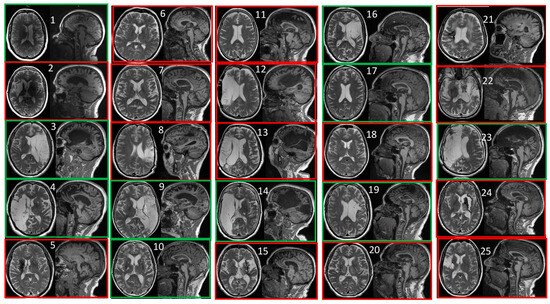

2.7. MRI Assessment and Segmentation